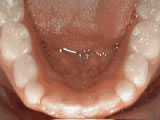

SPACING OF TEETH

spacing of teeth beforeBEFORE

spacing of teeth afterAFTER

Patient was bothered by the spaces between his teeth. Braces closed the spaces and gave him an ideal bite in 24 months. Special glued-in retainers help keep the spaces closed.